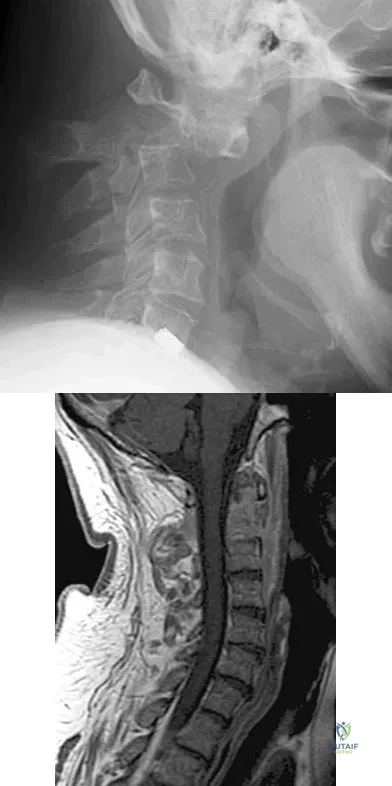

A 29-year-old man reports a 2-week history of severe neck pain after being struck sharply on the back of the head and neck while moving a refrigerator down a flight of stairs. Initial evaluation in the emergency department revealed no obvious fracture and he was discharged in a soft collar. Neurologic examination is within normal limits, and radiographs taken in the office are shown in Figures 21a through 21c. Subsequent MRI scans show intra-substance rupture of the transverse atlantal ligament. What is the most appropriate treatment option at this time?

Explanation